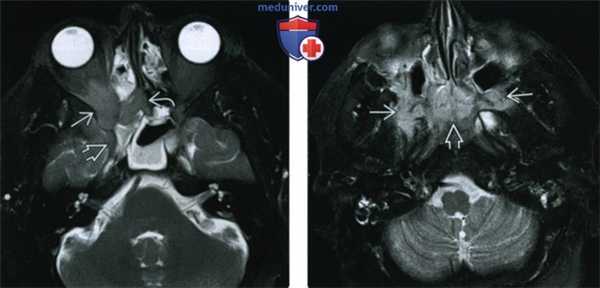

(Слева) У пациента с болезненным неподвижным правым глазом при МРТ Т1ВИ FS с КУ в корональной проекции внутри и вне мышечного конуса определяется обширная зона контрастирования с нечеткими контурами. Глазодвигательные мышцы увеличены в размерах, их контуры также нечеткие. Обратите внимание на инфильтрацию вокруг влагалища зрительного нерва.

(Справа) При аксиальной МРТ Т2 ВИ у этого же пациента в правой глазнице определяется гипоинтенсивная зона инфильтрации с нечеткими контурами. Слабый Т2-сигнал указывает на хронический фиброз, вызванный склерозирующим идиопатическим воспалением глазницы (псевдотумором). Обратите внимание: неподвижный глаз отклонен кнаружи.

(Слева) У пациента с ограничением подвижности глазного яблока при MPT Т1 ВИ FS с КУ в коро-нальной проекции в левой глазнице внутри и вне мышечного конуса визуализируется плохо контрастируемая инфильтративная ткань, отмечается небольшое увеличение размеров глазодвигательных мышц. В этом случае комплексная терапия оказалась эффективной.

(Справа) У пациента с болями в области лица и офтальмоплегией при МРТ Т1BИ FS с КУ в корональной проекции определяется выбухание твердой мозговой оболочки латеральной стенки и контрастирование правого кавернозного синуса по сравнению с контрлатеральным кавернозным синусом. Обратите внимание на уменьшение калибра кавернозного сегмента внутренней сонной артерии. Синдром Tolosa-Hunt.